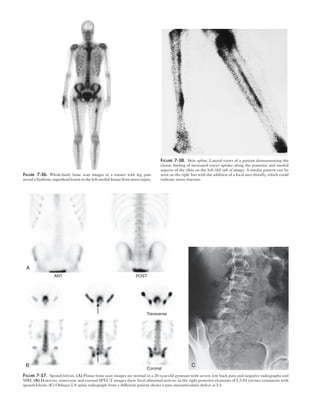

Figure 7-38. Shin splint. Lateral views of a patient demonstrating the

classic finding of increased tracer uptake along the posterior and medial

aspects of the tibia on the left (left side of image). A similar pattern can be

seen on the right, but with the addition of a focal area distally, which could

indicate stress fracture.

Transverse

B C

Coronal

A

Figure 7-37. Spondylolysis. (A) Planar bone scan images are normal in a 20-year-old gymnast with severe low back pain and negative radiographs and

MRI. (B) However, transverse and coronal SPECT images show focal abnormal activity in the right posterior elements of L5-S1 (arrow) consistent with

spondylolysis. (C) Oblique LS spine radiograph from a different patient shows a pars interarticularis defect at L5.